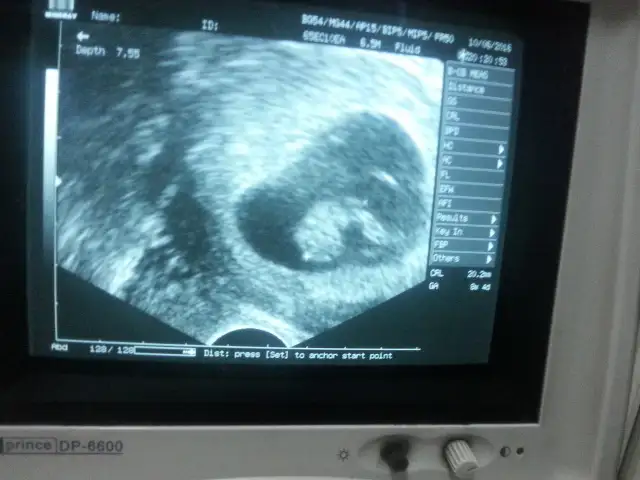

6+0 vajinal 8+0 karından 8+2 vajinal

Eki Görüntüle 1846894 Eki Görüntüle 1846895 Eki Görüntüle 1846896